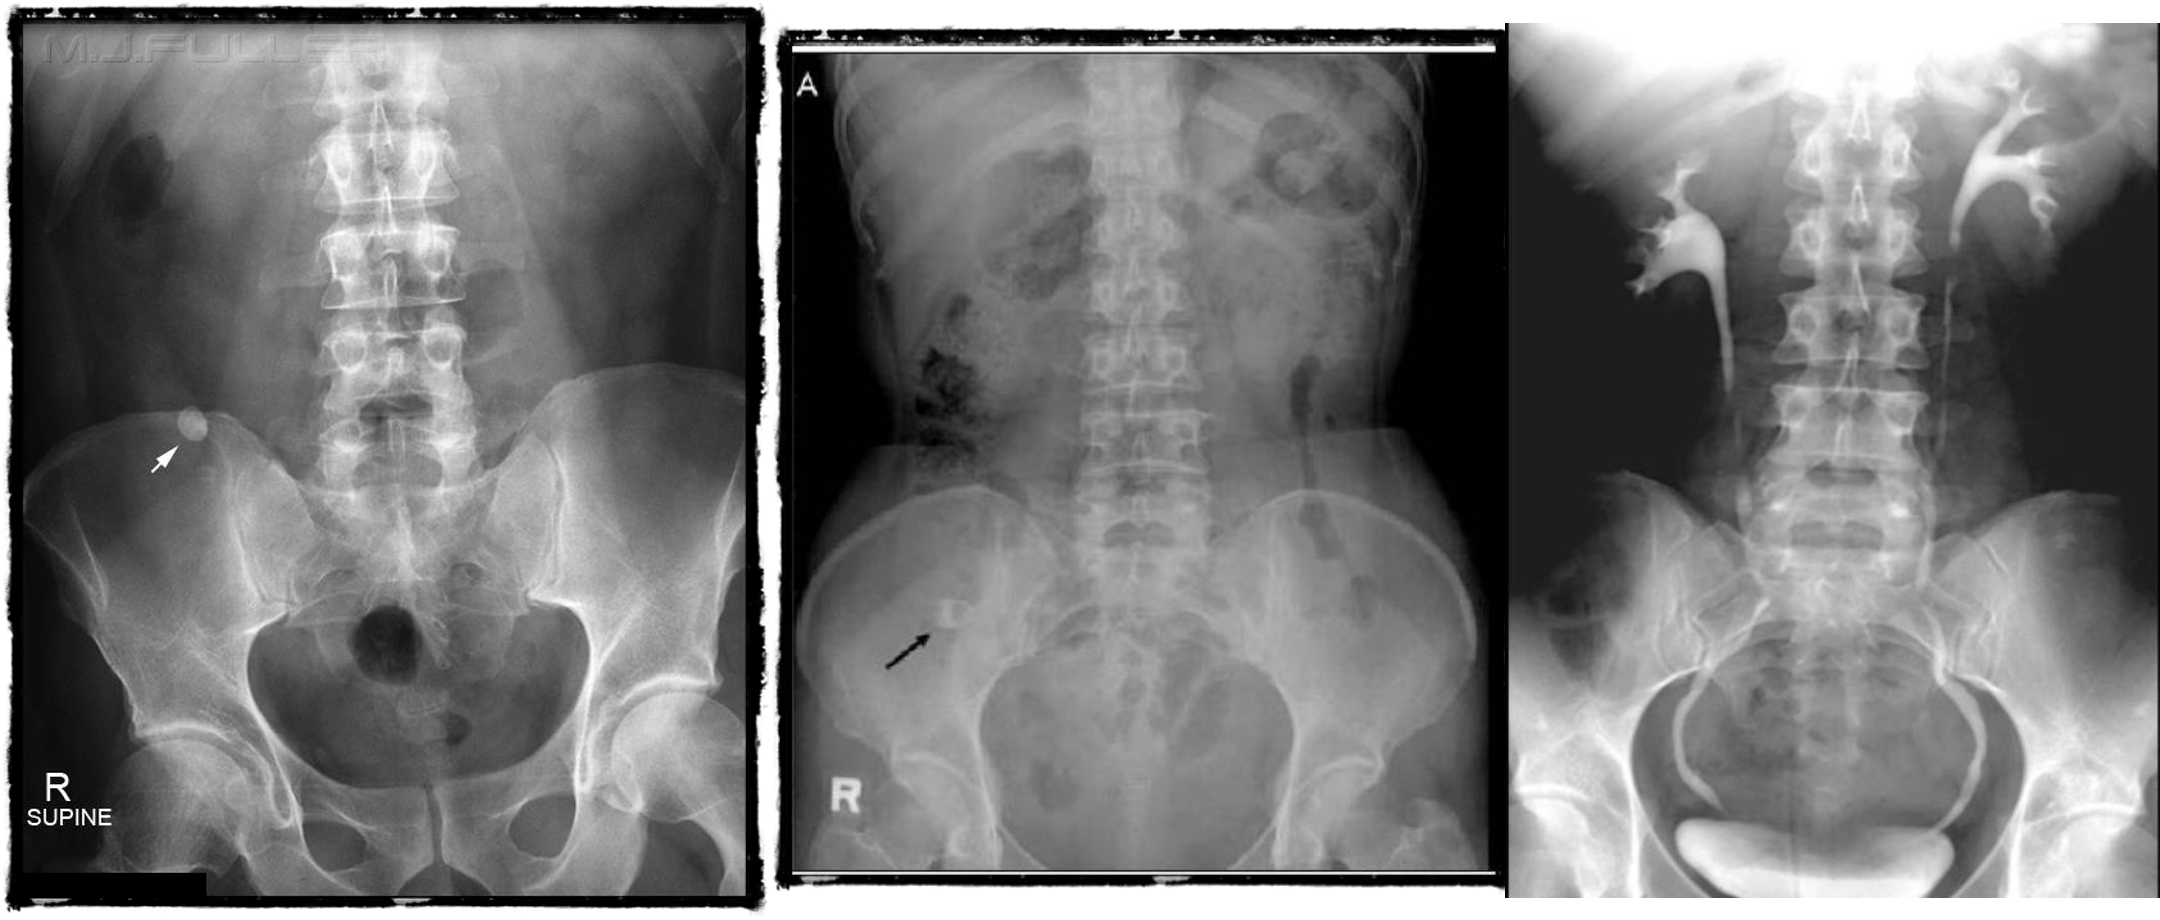

- & 2 Appendicitis - appendicolith/feacolith in young, MALT GALT

- Uretic stone

- radioopaque shadow on RUQ - renal stone

- Gallstone illeus - radioopaque shadow (regulars triad??)